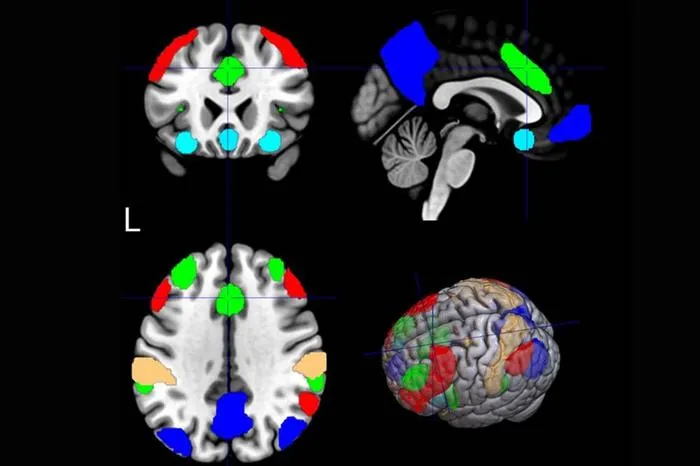

MUSC researchers used machine learning on fMRI scans to predict which smokers would benefit from repetitive transcranial magnetic stimulation (rTMS) for quitting smoking.

- 3The salience network's connectivity in the brain, analyzed by AI, correlated best with positive rTMS outcomes.